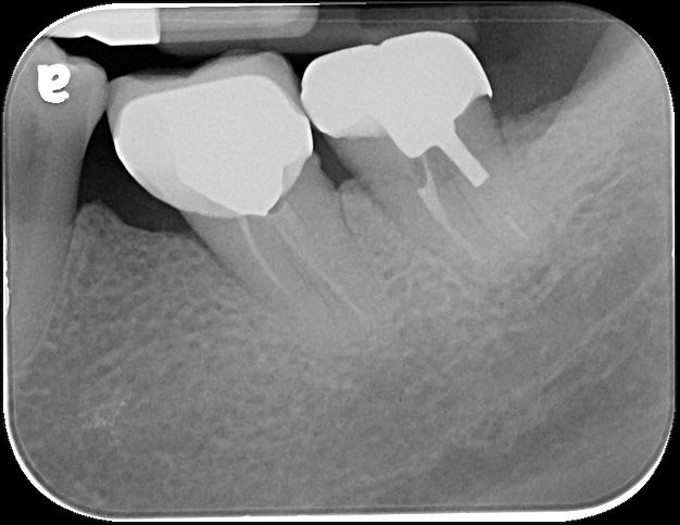

治療後X光再次檢查密合性